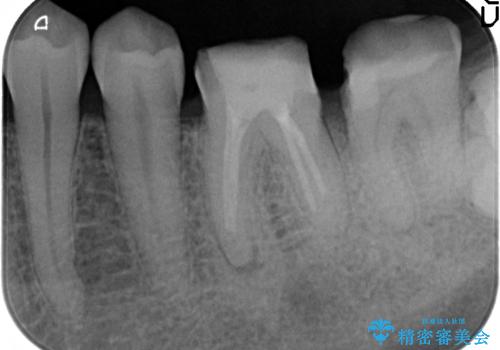

- 左下7の歯しみる、被せ物を被せてもすぐに外れてしまうといらっしゃった方の症例です。

左下に被せ物を被せるクリアランス(補綴のための上下のスペース)ないため、十分な歯冠長を確保するため歯冠長延長術を行いました。

その後歯肉の回復を待ち、フルジルコニアクラウンにて補綴を行いました。

歯冠長延長術とは歯肉弁根尖側移動術とも言い、歯の高さが低くクラウン(被せ物)による治療が難しい場合に、歯茎を歯根方向に下げることで歯の高さを確保する手術です。歯の高さが十分にあることで、外れにくいしっかりとしたクラウンを被せることができます。